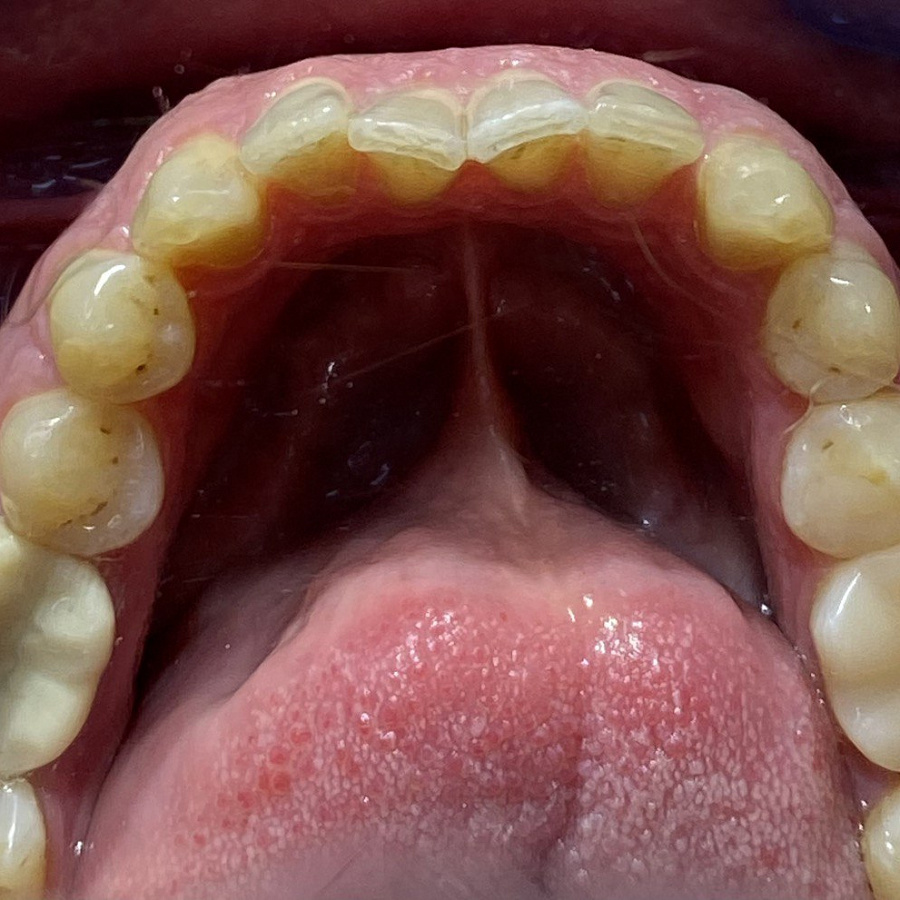

Пациент обратился с жалобами на неровные передние зубы верхней и нижней челюстей.

сужение зубных рядов,

обратное перекрытие в области фронтальных зубов слева,

разворот по оси передних зубов верхней и нижней челюстей,

стираемость эмали зубов,

индивидуальную микродентию 12 и 22 зубов.

Ортодонтическое лечение с помощью элайнеров длилось 10 месяцев. Далее последовало протезирование и установка виниров.

Результат лечения